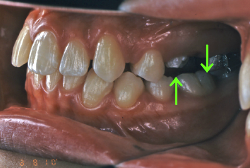

「ものがうまく噛めない」という主訴で来院したケースです。診断の結果、「骨格性反対咬合に伴う咬合不良+軽度叢生」と判明しました。原因としては特に下顎の左側が過成長したため、骨格性反対咬合になり、特に左側での噛み合わせが非常に悪くなっていると診断しました。初診時の写真を見ると、上下の正中線の大きなズレ、左側の噛み合わせの不良がはっきり分かります(黄色の矢印と緑の矢印は一致しているのが正しい状態です)。

そもそも、このような状態となっているのは骨の大きさに問題があるため生じていますので、場合によっては、「外科矯正」によって下顎の骨を外科的に縮めることで修正します。患者様が外科矯正をご希望されない場合は、従来ですと上下左右の小臼歯抜歯を行い矯正するのが普通です。

今回の患者様の場合は、「外科」も「小臼歯抜歯」も拒否されましたので、歯科矯正用アンカースクリュー(以下 アンカースクリュー)を用いて、下顎の歯列全体を後方に下げるという方法を取りました。

治療中の写真で、アンカースクリューより歯を後ろへ牽引しているのがお分かりいただけるかと思います。牽引を1年ほど続け、途中補助的に上下にゴムをかける(これを顎間ゴムと言います)手法なども追加し、全体で21ヶ月で治療を終えることが出来ました。

結局歯の本数を減らすことなく、すべてご自分の歯を残して、正しい配列と噛み合わせにすることができました。凸凹があまりひどくないため、簡単そうに見えると思いますが、このケースの初診の状態を見ると、熟練の矯正歯科医でも悩みのつきないケースです。まして、外科も出来ない、抜歯もイヤ、と言うことになると、従来の方法では治療不可能と考えられるのですが、アンカースクリューを使うことで最近は不可能が可能となってきました。